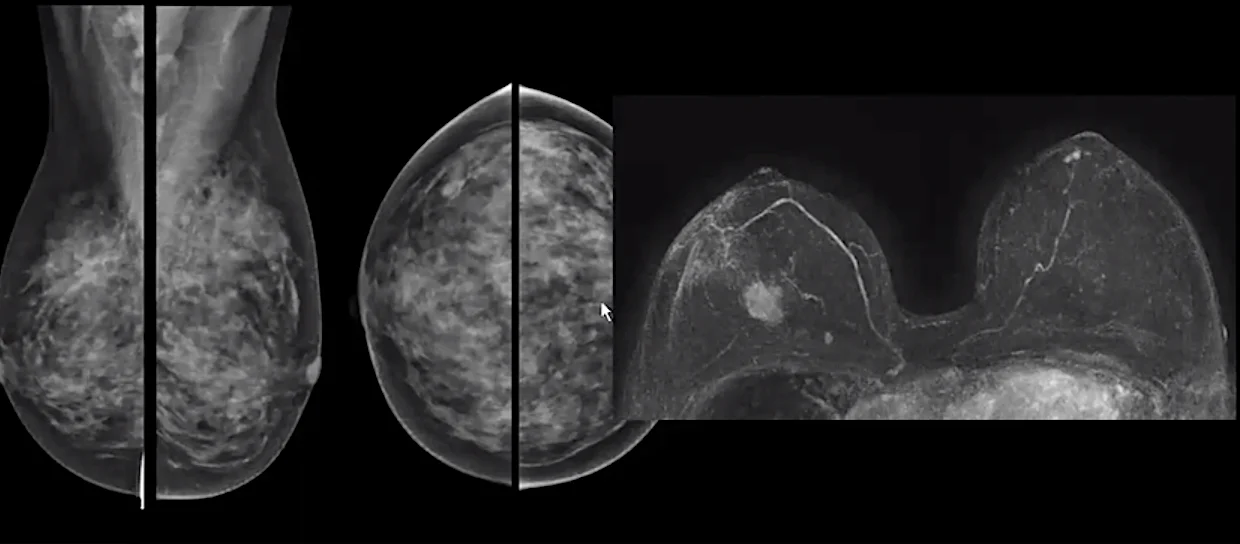

Στα πλαίσια των προληπτικών εξετάσεων, αλλά κυρίως της περαιτέρω διερεύνησης, εντάσσεται και η Μαγνητική Μαστών.

Η Μαγνητική Μαστών είναι μια εξέταση Μαγνητικής Τομογραφίας που διαρκεί συνήθως 20 – 30 λεπτά και προϋποθέτει την χορήγηση σκιαγραφικής ουσίας. Έτσι μπορεί να αναδείξει ευρήματα που δεν είναι εμφανή στην Μαστογραφία και τον Υπέρηχο και να βοηθήσει στην έγκαιρη διάγνωση ενός καινούριου καρκίνου σε μια μέχρι πρότινος υγιή γυναίκα ή ακόμα και σε γυναίκες με γνωστό

καρκίνο να αναδείξει την πραγματική του έκταση ή ένα δεύτερο καρκίνο στον άλλο μαστό που χρειάζεται επίσης να αντιμετωπιστεί. Με αυτό τον τρόπο γίνεται ορθότερος προγραμματισμός του χειρουργείου ώστε να αφαιρεθεί όλη η νόσος χωρίς να μείνουν υπολείμματα ή αλλοιώσεις που μπορεί να εξελιχθούν σε καρκίνο στο μέλλον.

Η Μαγνητική Μαστών αποκτά όλο και σημαντικότερο ρόλο στις προληπτικές εξετάσεις για τον καρκίνο του μαστού. Δηλαδή υγιείς γυναίκες χωρίς συμπτώματα από τον μαστό, αλλά με πραγματικά βεβαρυμένο οικογενειακό ιστορικό ή και διαγνωσμένη γενετική προδιάθεση για καρκίνο του μαστού (φορείς ογκογονιδίου) υποβάλλονται σε προληπτικό έλεγχο με Μαγνητική

Μαστών σύμφωνα με τις κατευθυντήριες οδηγίες. Τα τελευταία χρόνια και μετά από συστάσεις από αρμόδιες επιτροπές του εξωτερικού (EUSOBI-European Society of Breast Imaging) οι γυναίκες με πυκνό μαστό και χωρίς κανένα άλλο προδιαθεσικό παράγοντα, εξετάζονται προληπτικά και με Μαγνητική Μαστών ανά 2-4 χρόνια αφού στις γυναίκες αυτές ένας πιθανός καρκίνος θα ήταν πολύ πιο δύσκολα ορατός στην Μαστογραφία.

Η Μαγνητική Μαστών είναι πολύτιμο εργαλείο στην προσπάθεια για έγκαιρη διάγνωση του καρκίνου του μαστού. Είναι όμως μια εξειδικεύμενη εξέταση που για να αποδώσει χρειάζεται να εκτελείται από έμπειρο προσωπικό, σε μηχάνημα τελευταίας τεχνολογίας – ιδανικά σε Μαγνητικό Τομογράφο 3 Τέσλα- και να διαγιγνώσκεται από εξειδικευμένους στο αντικείμενο ιατρούς Ακτινολόγους.